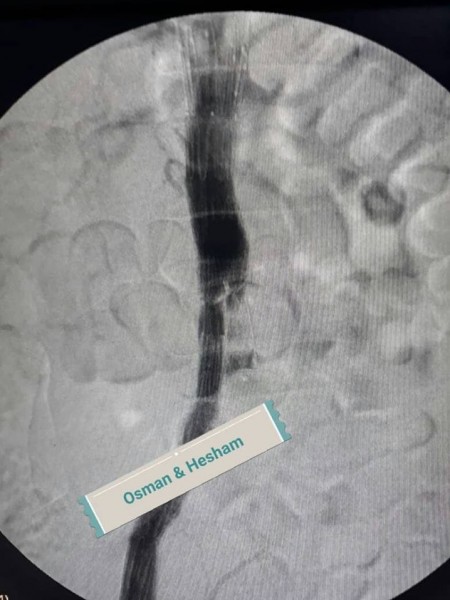

وحول خطوات الجراحة أضاف الدكتور عثمان انه فور إجراء أشعه الدوبلكس للمريض على للشريان الحرقفى الأيسر والشريان الأورطى تبين وجود تمدد ووجود قرحه نشطة بالشريان مع تصلبات شديدة غير مستقرة وانسداد بالدعامة السابقة وكذلك تم إجراء أشعه مقطعية على الشريان الأورطى والطرفين بالصبغة والتي أكدت نفس النتائج ، فكان القرار استخدام دعامات مغطاة للشريان الأورطى والشريان الحرقفى الأيمن وذلك نظراً لأن الوضع الصحي للمريض لا يسمح بإجراء تدخلات جراحية للشريان الأورطى ، ثم تم عمل زرع شريان من الطرف الأيمن للطرف الأيسر لصعوبة شق الدعامة السابقة لاختلاف كبير فى المقاسات التي تم تركيبها للمريض فى وقت سابق .